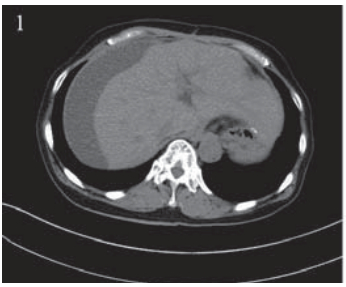

患者,女,66岁。2011年12月因“进食哽噎3 月余”就诊,查胃镜:贲门大弯后壁可见一大小约 3.5 cm×3.9 cm的不规则溃疡,周边堤样隆起。全 身CT等检查提示无其他部位转移,遂于2011年12 月22日在上海中山医院行贲门癌根治术,术中探 查见贲门部病灶,约3 cm×4 cm,质地中等,周围 脏器未见异常,遂行贲门癌根治术,食管胃机械 吻合。术后病理:“贲门”溃疡型腺癌,Ⅱ~Ⅲ级, 侵及胃壁全层及周围脂肪组织,淋巴结(3/20) 见癌转移。TNM分期为:ⅢB期(T4aN2M0), 术后复查CT:两肺少许间质性改变,后腹膜淋巴 结稍大,右肾上极局部形态异常,伴右肾囊肿。 2012年1月27日起予“奥沙利铂+替吉奥”化疗六周 期,期间复查CT无转移依据。2012年8月再次复 查CT:左肺叶间胸膜增厚,右肺上叶可疑小结 节,胃癌术后改变,肝脏小囊肿可能,肝右叶包 膜下包裹性积液,右肾上极梗死后遗改变可能, 右肾小囊肿、小结石,腹盆腔积液,见图 1。查 CA199:154.71 IU/ml,CEA:15.65 ng/ml,肿瘤 进展,遂予“紫杉醇+替吉奥”化疗一周期。2012 年11月初患者出现右上腹胀痛,进食后明显,伴 恶心、呕吐,呕吐物为胃内容物。遂入住我科。 入院查体:右上腹可触及包块,有压痛,中上腹 部可见陈旧性手术疤痕,肝区叩痛明显,余未 见异常。血常规、肝肾功能正常。CA199:143.3 IU/ml,CEA:16.56 ng/ml。腹腔B型超声:腹腔 积液,最大前后径约26 mm;肝包膜下巨大囊性 占位,大小约16.3 cm×9.5 cm,见图 2 。胸部CT未 见异常。腹盆部CT:胃癌术后改变,肝脏小囊肿 可能,肝右叶包膜下包裹性积液较前明显增加, 右肾上极梗死后遗改变可能,右肾小囊肿、小结 石,右肾轻度积水,腹盆腔积液,见图 3。

图 1 肝包膜下巨大囊性转移瘤患者腹部CT Figure 1 Abdominal CT of huge cystic metastatic tumor of hepatic subcapsular The encapsulated fluid under the right lobe of the liver capsule |